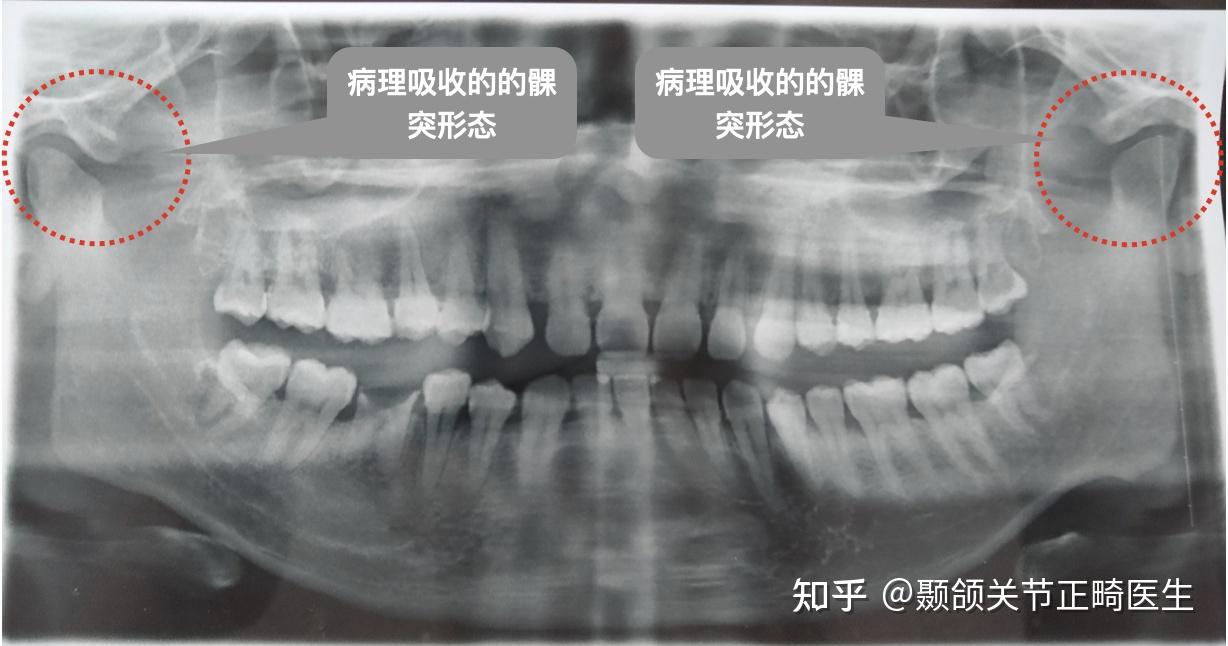

tmd颞下颌关节炎早期症状是啥,颞下颌紊乱脸歪能做矫正改善m

颞下颌关节紊乱案例 | 电影看到一半,嘴巴合不上了

左侧下颌角周围软组织积气;右侧颞下颌关节向前移位.